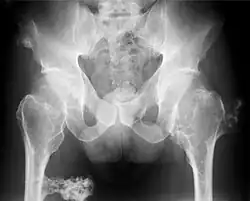

- Subluxation des Hüftgelenkes infolge Herausdrängens des Hüftkopfes durch den nach medial sich exostotisch verbreiternden Schenkelhals